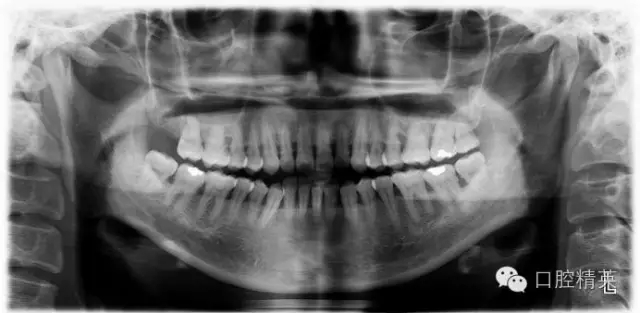

本病例 :女 34歲,主訴刷牙出血,覺(jué)牙齒輕度松動(dòng)一年。

檢查見(jiàn)大量齦上及齦下結(jié)石,探診出血,牙周袋較深,32-42 II度松動(dòng)。X線片顯示牙槽骨水平吸收。

診斷:成人慢性廣泛性中度牙周炎。

治療前:

X-ray: